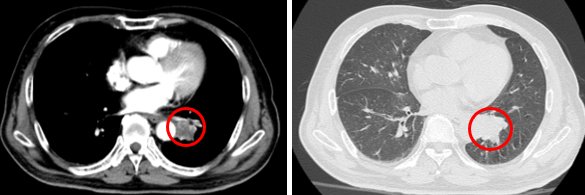

Hình 1: Hình ảnh chụp CT lồng ngực: Nhu mô thùy dưới phổi trái sát rốn phổi có nốt kích thước 24x26 mm bờ không đều, sau tiêm ngấm thuốc (vòng tròn đỏ), hình ảnh cắt cụt nhánh phế quản thùy dưới.